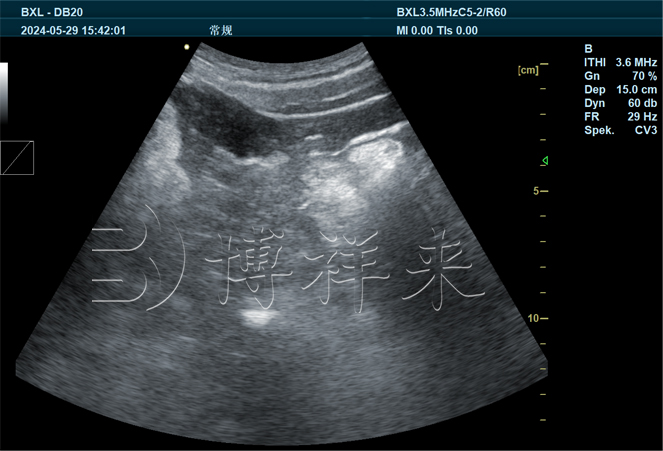

博祥来生产的B超机设备采用超声波检测技术,可以在猪只体内进行精准扫描,实现以下几方面的关键应用:

早期妊娠诊断:B超机能够在猪只排卵后短时间内检测出妊娠状态,使得生殖管理更加科学、及时。

生殖系统评估:通过检测猪只子宫、卵巢等部位,为精准确定受孕猪只提供有效依据,减少误诊率。

- 早期疾病预警:B超机检测能及时识别猪只体内异常,例如卵巢囊肿或子宫病变,帮助尽早进行治疗干预。

- 精准性高:采用高频超声波探头,分辨率高达0.1mm,确保检测数据精准无误,降低人为误判风险。